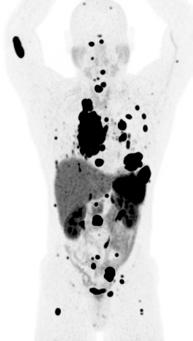

The researchers report on their work in “Tissue-based T cell activation and viral RNA persist for up to 2 years after SARS-CoV-2 infection” published as the cover story in Science Translational Medicine (Vol. 16, No. 754).

First author Michael Peluso, MD, and senior authors Henry F. VanBrocklin, PhD, and Timothy Henrich, MD, in collaboration with a team of multidisciplinary researchers, used whole-body positron emission tomography (PET) imaging with the innovative radiopharmaceutical agent [18F]F-AraG from Cellsight Technologies. This agent is pivotal in mapping activated T lymphocytes in the body, providing a unique insight into immune responses following SARS-CoV-2 infection. The study included a cohort of 24 participants, imaged between 27 to 910 days post-infection, offering a broad perspective on the temporal dynamics of Long Covid.

Imaging Long COVID. The cover shows severe acute respiratory syndrome coronavirus 2 (SARSCoV-2) spike protein–encoding single-stranded RNA (ssRNA, green) in rectosigmoid tissue collected from an individual with Long COVID nearly 2 years after their acute SARS-CoV-2 infection. Nuclei are shown in blue. Peluso et al. performed whole-body positron emission tomography imaging with a tracer that tags activated T cells in a cohort of 24 individuals up to 910 days after acute SARS-CoV-2 infection. The authors found that individuals with Long COVID symptoms had more tracer uptake than those without symptoms, including in the gut. Further, rectosigmoid tissue collected from five participants with Long COVID consistently harbored SARS-CoV-2 spike protein-encoding ssRNA. These data suggest that ongoing T cell activation and viral persistence may be drivers of Long COVID.

The study results are compelling. Participants with postacute COVID-19 exhibited heightened [18F]F-AraG uptake compared to pre-pandemic controls in several anatomical regions, notably the brain stem, spinal cord, bone marrow, lymphoid tissues, cardiopulmonary areas, and the gut wall. This elevated uptake highlights increased T cell activation, a marker of immune system engagement.

Interestingly, T cell activation in the spinal cord and gut wall was closely linked with LC symptoms. Persistent pulmonary symptoms correlated with increased lung tissue activation. These observations were consistent even in participants without overt LC symptoms, indicating a broader immune response pattern post-infection.

In a subset of five participants with LC symptoms, colorectal tissue analysis revealed the presence of SARSCoV-2 RNA. Single-stranded spike protein-encoding RNA was detected in the rectosigmoid lamina propria tissue of all five participants, with double-stranded RNA found in three. This finding, observed up to 676 days post-infection, suggests a potential link between viral persistence and long-term immune disturbances.